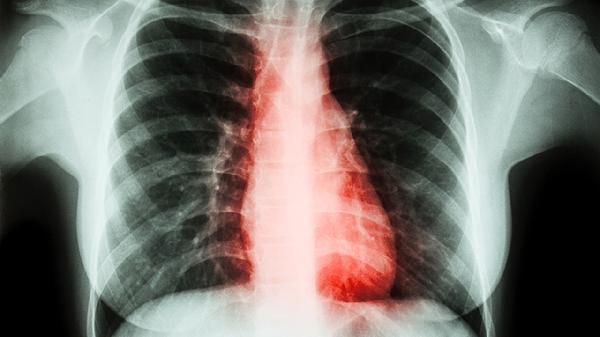

肺结节是一种常见的肺部异常,可能是良性或恶性的,但多数情况下属于良性。要了解肺结节的严重程度,需通过详细的检查和诊断判定,常见的检查方法包括CT扫描和活检。接下来,我们将从遗传因素、环境因素、生理因素、外伤和病理方面,详细分析肺结节的病因,并提供相应的处理建议。

1、遗传因素:虽然肺结节的遗传风险较低,但有家族肺癌史的人可能更易出现肺结节。对于这类人群,建议定期进行肺部X光或低剂量CT筛查,以便及早发现和处理异常。

2、环境因素:长期吸烟和生活在空气污染严重的环境中是导致肺结节形成的主要外部因素。戒烟和改善居住环境是减少肺结节发生的重要措施。当出现相关症状时,及时就医并根据医生建议进行进一步检查。